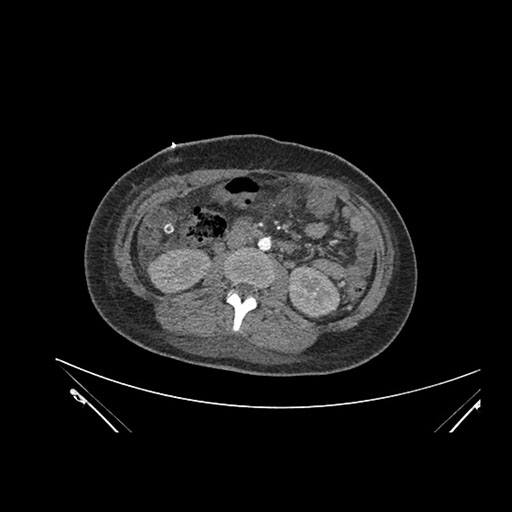

Imaging Analysis

Look through the patient's CT scan to identify any areas of concern for the necessary procedure.

Axial Arterial

Based on initial findings, which issue(s) would you be most concerned about?